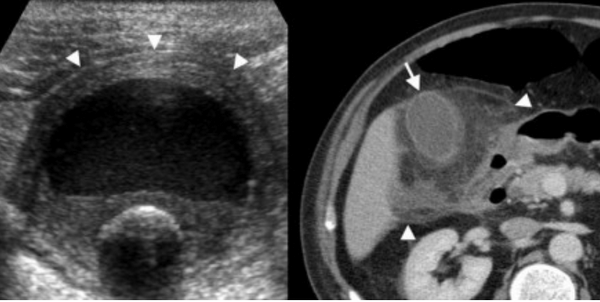

Сверху: УЗИ желчного пузыря стенка норма в виде «карандаша». Справа УЗИ картина псевдо-утолщения стенки желчного пузыря.

На КТ желчный пузырь в норме визуализируется, как образование с плотностью присущей мягким тканям. Указано стрелкой.

Утолщение стенки желчного пузыря — это частая диагностическая находка. Утолщением является размер стенки более 3 мм. При УЗИ утолщенная стенка имеет слоистый внешний вид, а на КТ выявляется гиподенсный слой, что соответствует субсерозному отеку.

Слева — УЗИ — желчного пузыря у 59 летней женщины с острым холециститом. Субсерозный отек так, как гипоэхогенное утолщение между гиперэхогенными слоями (мышечным и слизистым). Справа — КТ брюшной полости с контрастным усилением. Также визуализируется субсерозный отек так, как наружный слой гиподенсный.